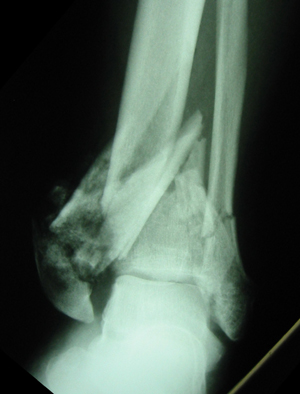

Pilon fracture

- Axial loading injury that drives tibial plafond (French for ceiling) into talar dome

- Also known as a tibial plafond fracture

- CT necessary to reveal amount of articular surface displacement/develop treatment plan